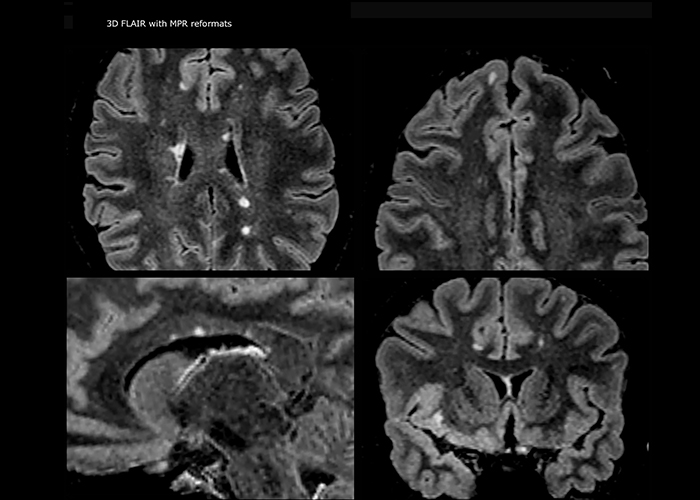

Multiple sclerosis imaging requires precision, speed

When multiple sclerosis (MS) is suspected, clinicians need a diagnosis early on, so treatment can begin as soon as possible. “A challenge for imaging is that MS lesions in the brain and spine may be very small,” says Dr. Savatovsky. “We need precise imaging to tell exactly where the lesion is, so we need high quality, very high resolution images, preferably in 3D[1]. We need to know if a high T2 signal intensity is suggestive of MS or just aspecific. And we want to visualize active lesions very well.”

“Ingenia 3.0T provides us very good image quality with high SNR, even if we push the resolution. For example, in FLAIR images we may have an isotropic resolution of 0.9 mm. Ingenia allows us to use 3D T1 TSE with BrainView, which has a better sensitivity than 2D spin echo imaging[2] and 3D gradient echo imaging. Ingenia also provides highly reproducible exams, which is important in MS imaging so that follow-up exams at different time points are done the same way.”

Imaging MS in brain

For MS imaging in the brain, Dr. Savatovsky uses 3D FLAIR as the basic sequence to visualize the lesions and assess the situation and lesion load. “We count the lesions in each location to determine if the criteria of the disease are fulfilled. We use a T2-weighted sequence because our neurologists are used to it. We compare the lesion load on FLAIR with a 3D T1 post-contrast sequence to help us determine whether lesions are old or new. We typically administer the contrast before the patient enters the machine because it shortens the examination time and allows to visualize active lesions that tend to be more visible after several minutes. When a differential diagnosis is difficult, we add sequences such as susceptibility imaging, because some focal MS lesions have a small vein in the center[3].”